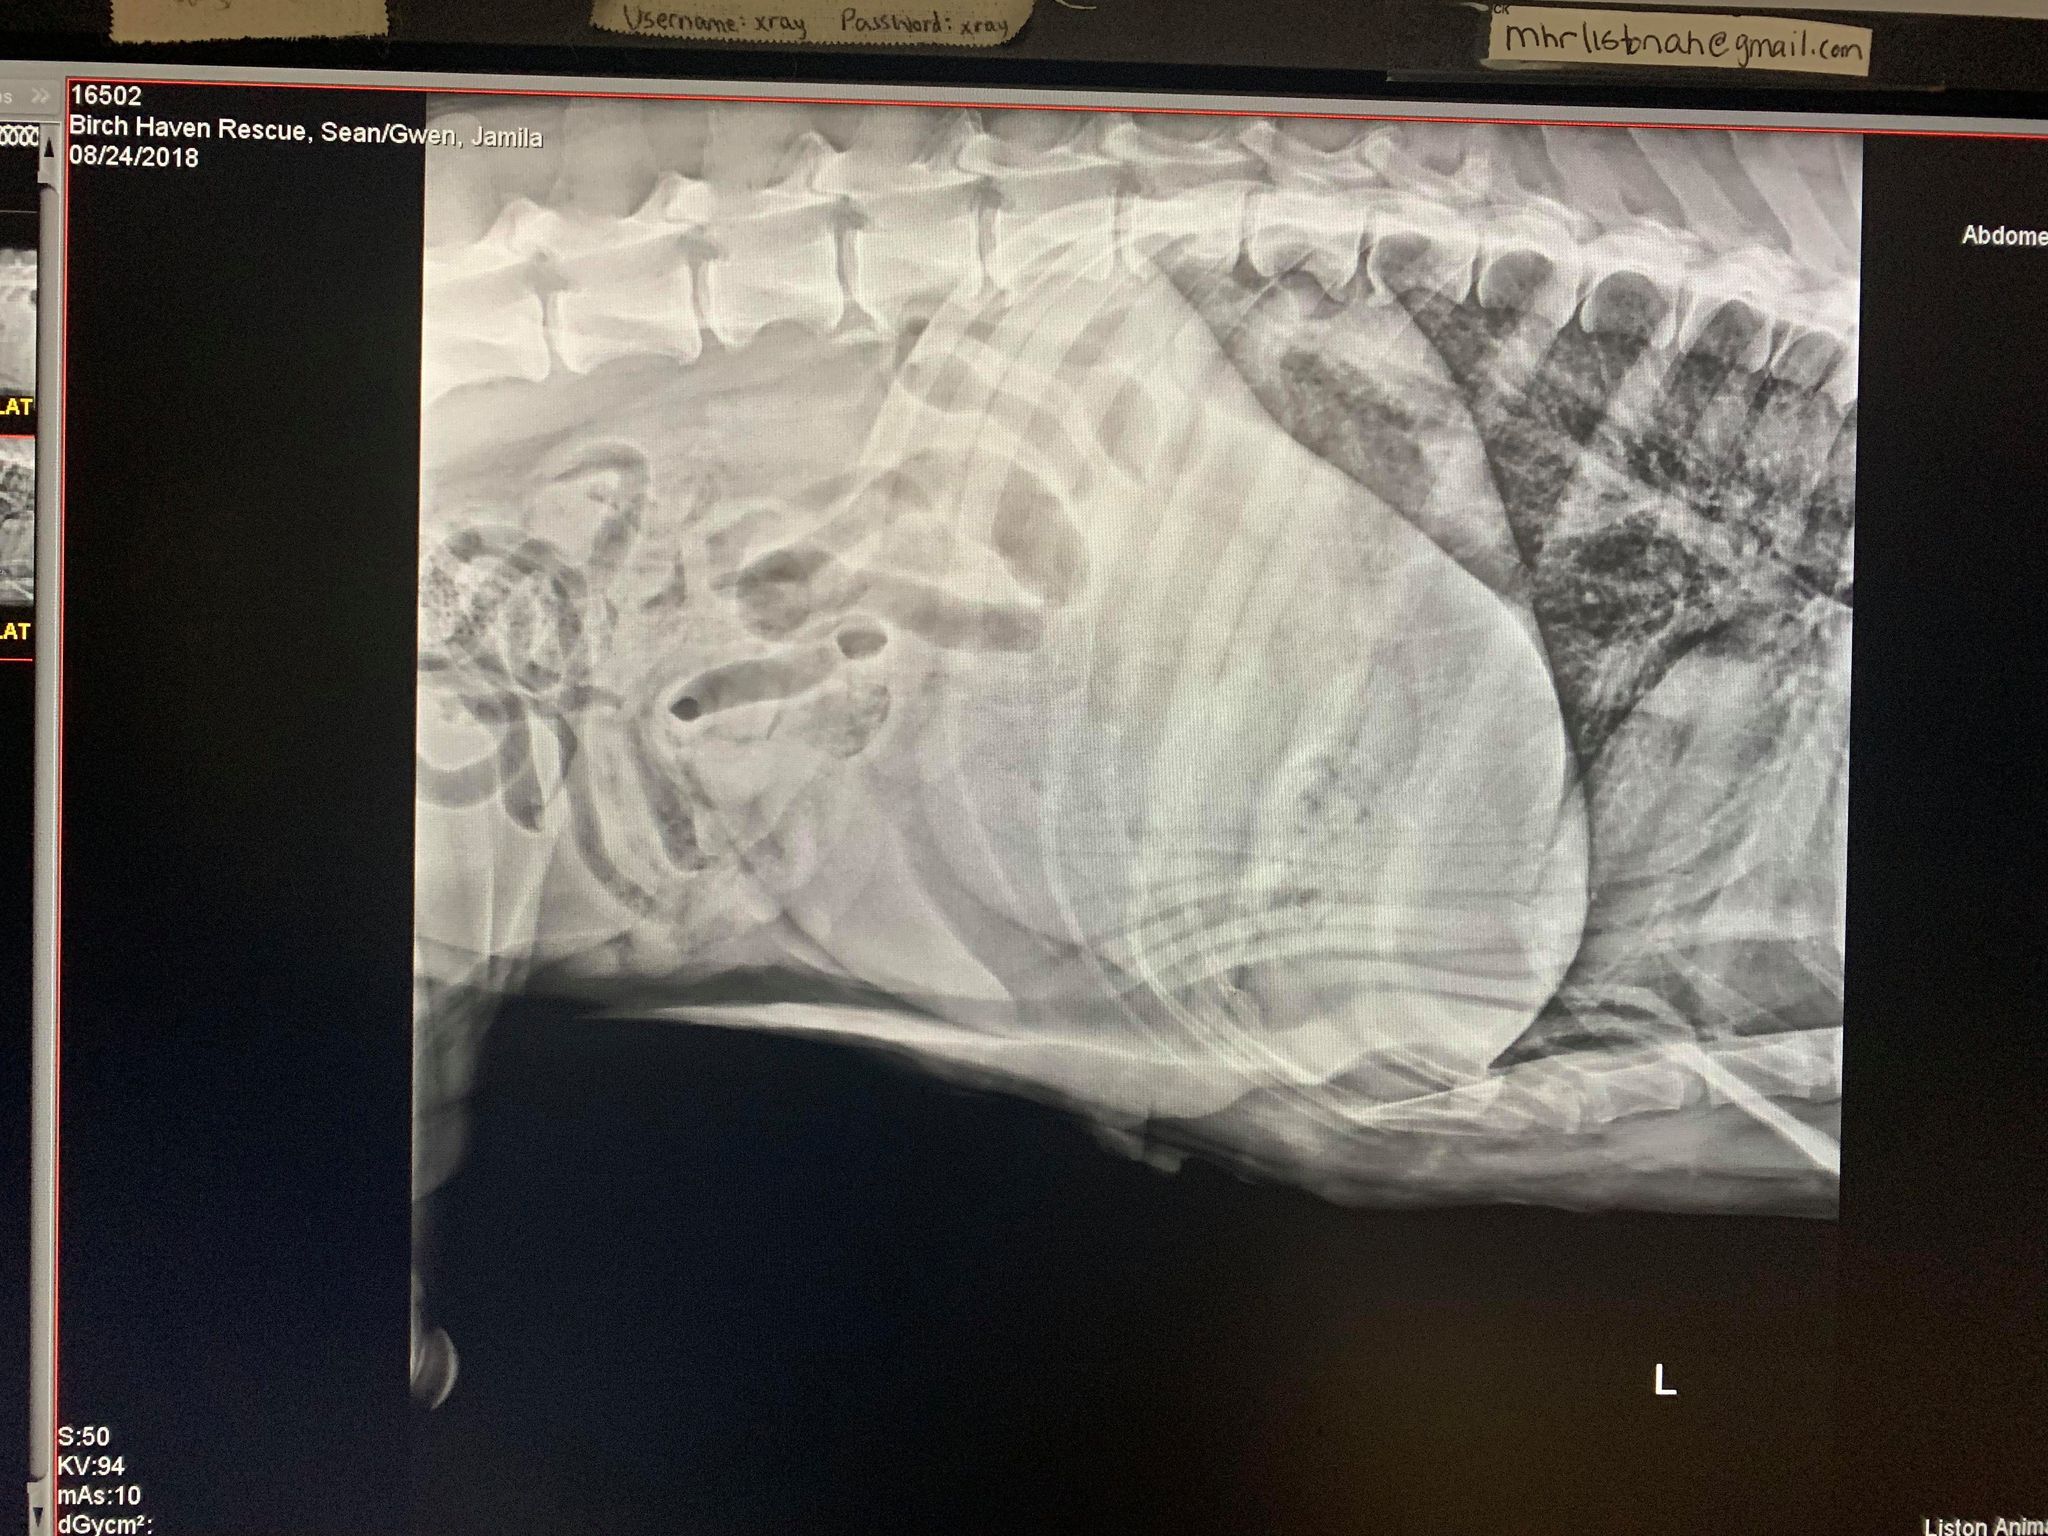

Miss Jamila!

A copy of her two x-rays.

Please assist us in surrounding her with a village of support and love!